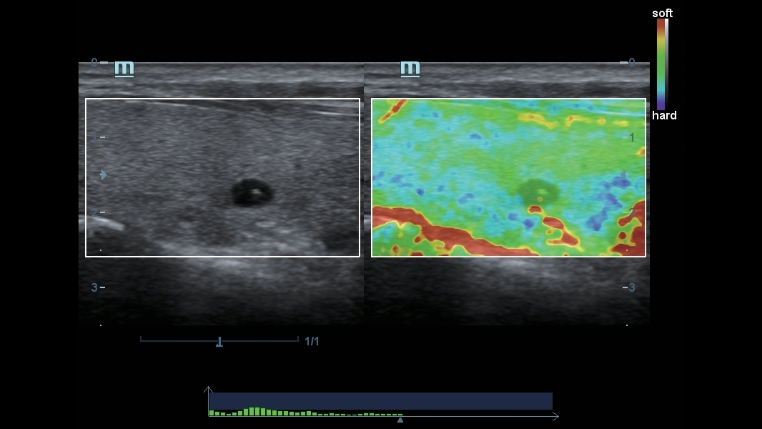

Diese bew?hrten Ultraschalltechnologien sorgen f├╝r eine h?here Diagnosequalit?t:

- iClear (Rauschunterdr├╝ckungs-Technologie)

- PSH (Harmonic Imaging mit Phasenverschiebung)

- iBeam: (Spatial-Compounding)

Der Einsatz anerkannter Bildgebungstechnologien macht das DC-40 mit Full HD sehr leistungsstark und hochwertig. Sie sind erfolgreich aus etablierten Ultraschallsystemen migriert worden. Eine clevere Kombination von Ultraschallsonden mit spezialisierten Schallk?pfen unterst├╝tzt erstklassige Ergebnisse in einem breiten Anwendungsspektrum. Mit Hilfe der Breitband-Schallk?pfe l?sst sich eine Vielzahl an Patiententypen erfolgreich untersuchen.